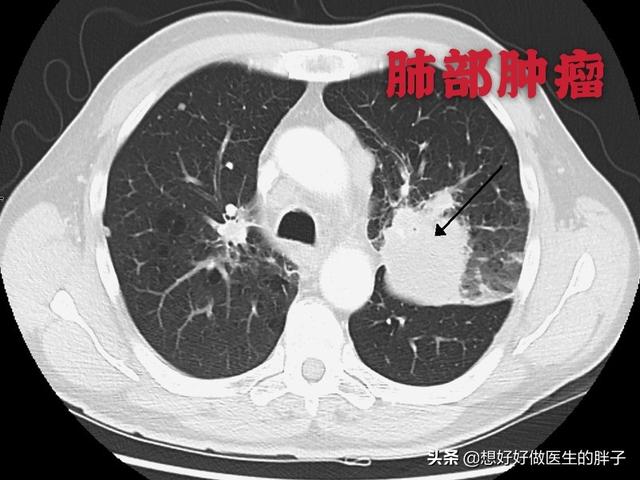

Ce nodule irrégulier dans le poumon gauche est le foyer principal, qui ne mesure que 2,6 cm. Un cancer du poumon avec des métastases osseuses comme celui-ci n'est plus opérable. On ne peut rien y faire, le cancer du poumon est trop fréquent et certains des premiers symptômes sont atypiques, voire asymptomatiques.Dans environ 30 % des cancers du poumon, les symptômes des métastases sont la première manifestation, et les métastases sont détectées en premier avant que d'autres cancers du poumon ne soient détectés.

Son examen tomodensitométrique le plus récent a montré que la photo primaire avait beaucoup rétréci et il a eu la chance de survivre avec une rétention pendant plus de 5 ans !